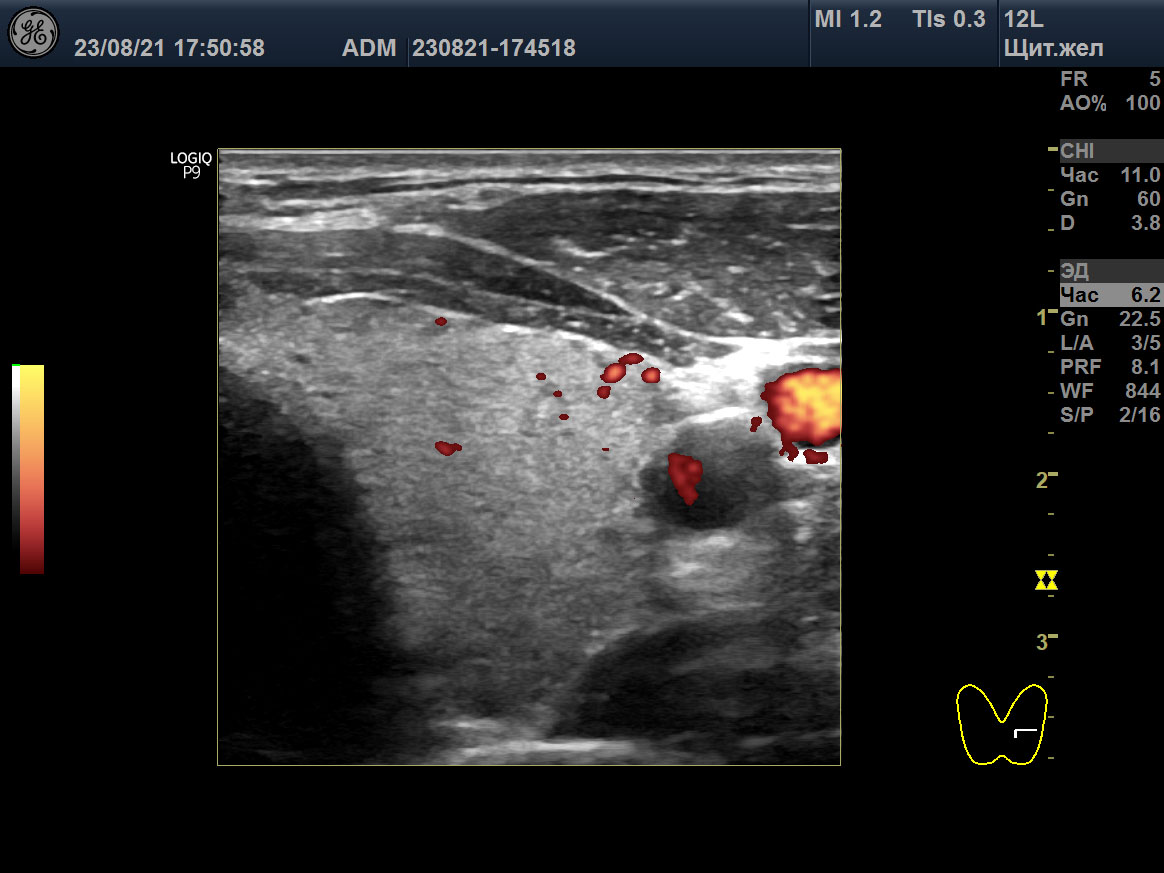

15 мая 2018 ультразвуковое исследование (УЗИ) щитовидной железы выявило зоб 3 степени (объём 45 мл; 23,6D + 21,4S), признаки умеренного отёка стромы (гомогенная гипоэхогенность паренхимы), значительное усиление интенсивности кровотока, систолическую пиковую скорость (SPV) кровотока в системе верхних щитовидных артериях (STA) 123 cm/sec справа и 160 cm/sec слева (рисунок: A, B, C).

A

B

C

D

E

F

Изображения щитовидной железы пациента в режиме Допплера. A, B, C ― до лечения (15 мая 2018), и D, E, F после лечения (23 августа 2021). A, D ― поперечная проекция левой доли. B, E ― продольная проекция левой доли. C, F ― SPV STA слева.

Вместе с тем, в августе 2021, при нормальном гормональном обмене и АТ-рТТГ 0,3 Ед/л (<1,5), объём щитовидной железы остался прежним (30,4 мл), у дорсального края в обеих долях сохранялись некоторые признаки отёка стромы, интенсивность кровотока с двух сторон в очень малой мере была усилена, улучшилась SPV STA – 27 cm/sec справа и 39 cm/sec слева (таблица 2; рисунок: D, E, F). В декабре 2022 ультразвук показал подобные признаки с незначительным улучшением: объем щитовидной 24 мл и преобладание изоэхогенной паренхимы.